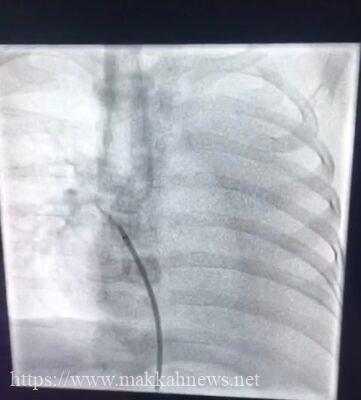

وأوضح مدير مركز أم القرى للقلب بمستشفى الولادة والأطفال بمكة الدكتور/ خالد أمين العطاس: من بداية الخطة العلاجية تم إعطاء الطفل أدوية لعلاج السوائل ثم تم فحصه بجهاز أشعة القلب “إيكو”تم إكتشاف وجود شريان زايد يأتي من الشريان الأورطي النازك إلى الأُذين الأيسر في القلب وهذه “القناة تعتبر من القنوات النادرة جداً” أن يكون مصب الدم من الأورطه مباشرة إلى الجهه اليسرى من القلب مباشرة وعليه تم عمل قسطرة تشخيصية لمحاولة إقفال القناة بجهاز خاص وتكللت العملية بنجاح ولله الحمد بفضل من الله .